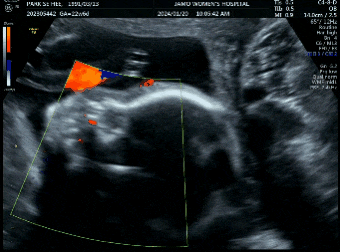

[임신 27,28주차] 3D입체초음파, 임신성당뇨검사, 진료결과

안녕하세요! 한방이맘이에요! 20주차의 마지막 검진이면서 하이라이트인 27주차 입체초음파를 보고왔어요~~...